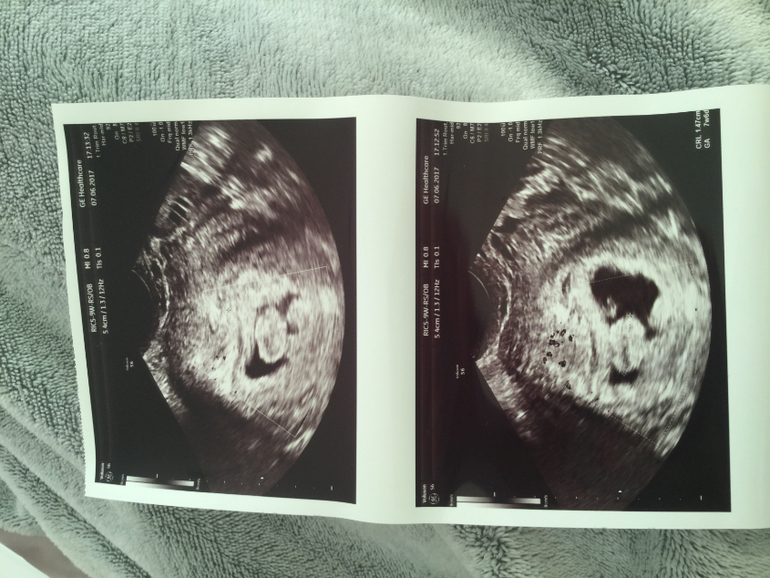

Помимо эмбриона в матке нашли какое то образование

Была только что у гинеколога, срок 6 недель, долго не мог найти эмбрион а потом увидел какое то пятно, опухоль, я не знаю.. сначала сказал что эмбрион может быть уже не живым, но сказал подождать до след недели, тогда будем смотреть и делать анализы( если все будет плохо то чистку) к слову, на прошлой неделе было только плодное яйцо, а теперь видно эмбрион, та и колбасит меня не по детс и, тошнит, рвёт, болит грудь ..год назад был выкидыш, так хотим ребёночка, может кто знает что это может быть, девоньки ??? А то реву без остановки ;((

добавила фото, а сб не слушали, он вообще долго найти плод не мог , потом сказал вроде опять зб, я начала плакать, потом нашёл ещё что то, говорит подождём, а там видно будет .. я ещё и в Польше живу, сама с мужем тут, если что будет не так то увольняюсь и еду домой, уже сил нет

честно, ничего не понимаю в этом, у вас какой то ячеистый эндометрий и что-то что есть в пя оно большое, но это не эмбрион, врачам тут виднее, желаю вам удачи и пусть вам все растолкует хороший врач!

Сказал что пя там сбоку справа. Но я в этом ничего не понимаю .спасибо большое